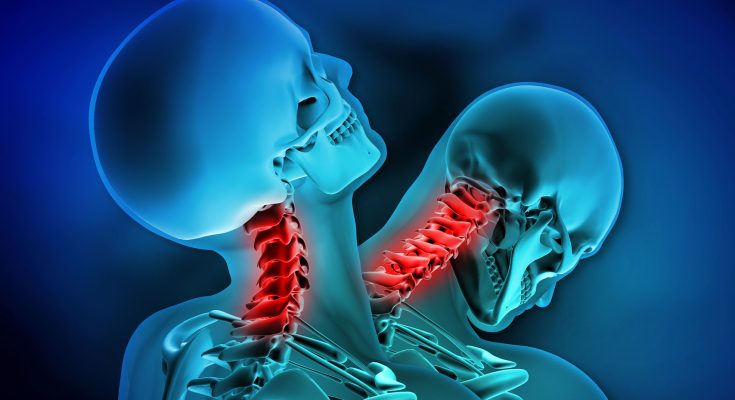

In September 2022, the Journal of Orthopaedic Case Reports published a troubling case involving an 18âÂÂyearâÂÂold male worker in India who sustained a severe cervical spine injury after a heavy metallic object fell directly on the front of his head while he was at work. This rare and catastrophic injury led to a retropulsion fracture of the C5 vertebral body, associated with a C6 fracture, and despite emergency care, the victim died two days later. This is the first recorded case of such injury morphology that defies standard classification systems.

Once in the emergency department, the patient underwent nonâÂÂcontrast computed tomography (NCCT) of the cervical spine. The images revealed:

An isolated retropulsion of the C5 vertebral body into the spinal canal.

Notably, no displacement of facet joints or pedicle fractures was seen.

A concurrent fracture in the posteroâÂÂsuperior portion of the C6 vertebral body was also identified.

Such an axial flexionâÂÂcompression injury, where the vertebral body is compressed and displaced backward (akin to a “nutcracker” effect), is exceptionally rare and has not been categorized within common classification systems such as Allen & Ferguson, SLICS, or AO Spine ([turn0search3], [turn0search0]). This was the first documented instance of this specific fracture pattern in medical literature.

The subaxial cervical spine (C3–C7) is structurally mobile, responsible for most neck movement. When force is applied along the head-to-spine axis, vertebral bodies such as C5 can be crushed between adjacent vertebrae. In this case, the downward force created a “nutcracker-like” compression that fractured C5 and drove it backward into the spinal canal, while also creating a secondary fracture at the superior posterior corner of C6 ([turn0search0], [turn0search3]).